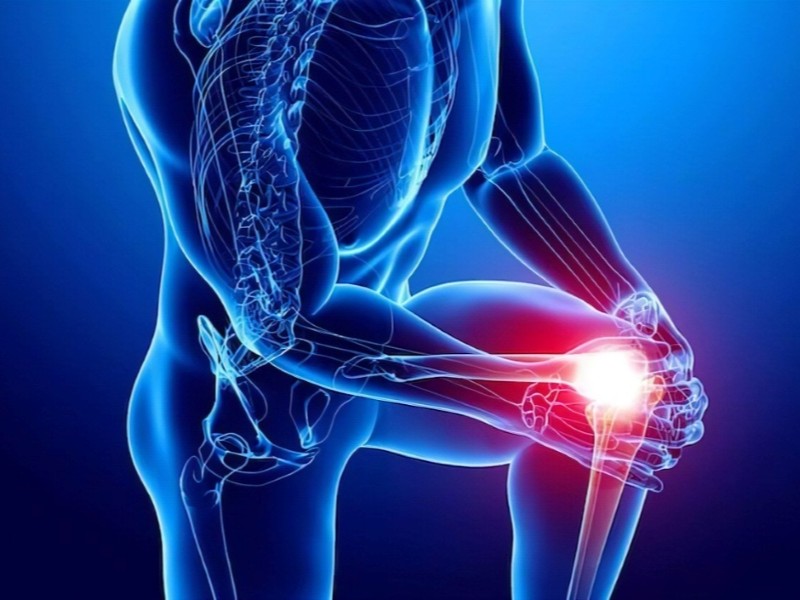

Le PRP est préparé à partir du sang du patient puis réinjecté afin de stimuler certains processus de régénération. En médecine esthétique et musculo-squelettique, il peut être proposé dans des cas tels que certaines tendinites, douleurs articulaires ou blessures sportives.

La clinique propose des infiltrations de cortisone sous guidage échographique. Cette technique médicale est utilisée pour soulager certains types d’inflammation et de douleurs, en fonction de l’évaluation clinique de chaque patient. La Régie de l'assurance maladie du Québec couvre tous les frais associés à ce traitement.